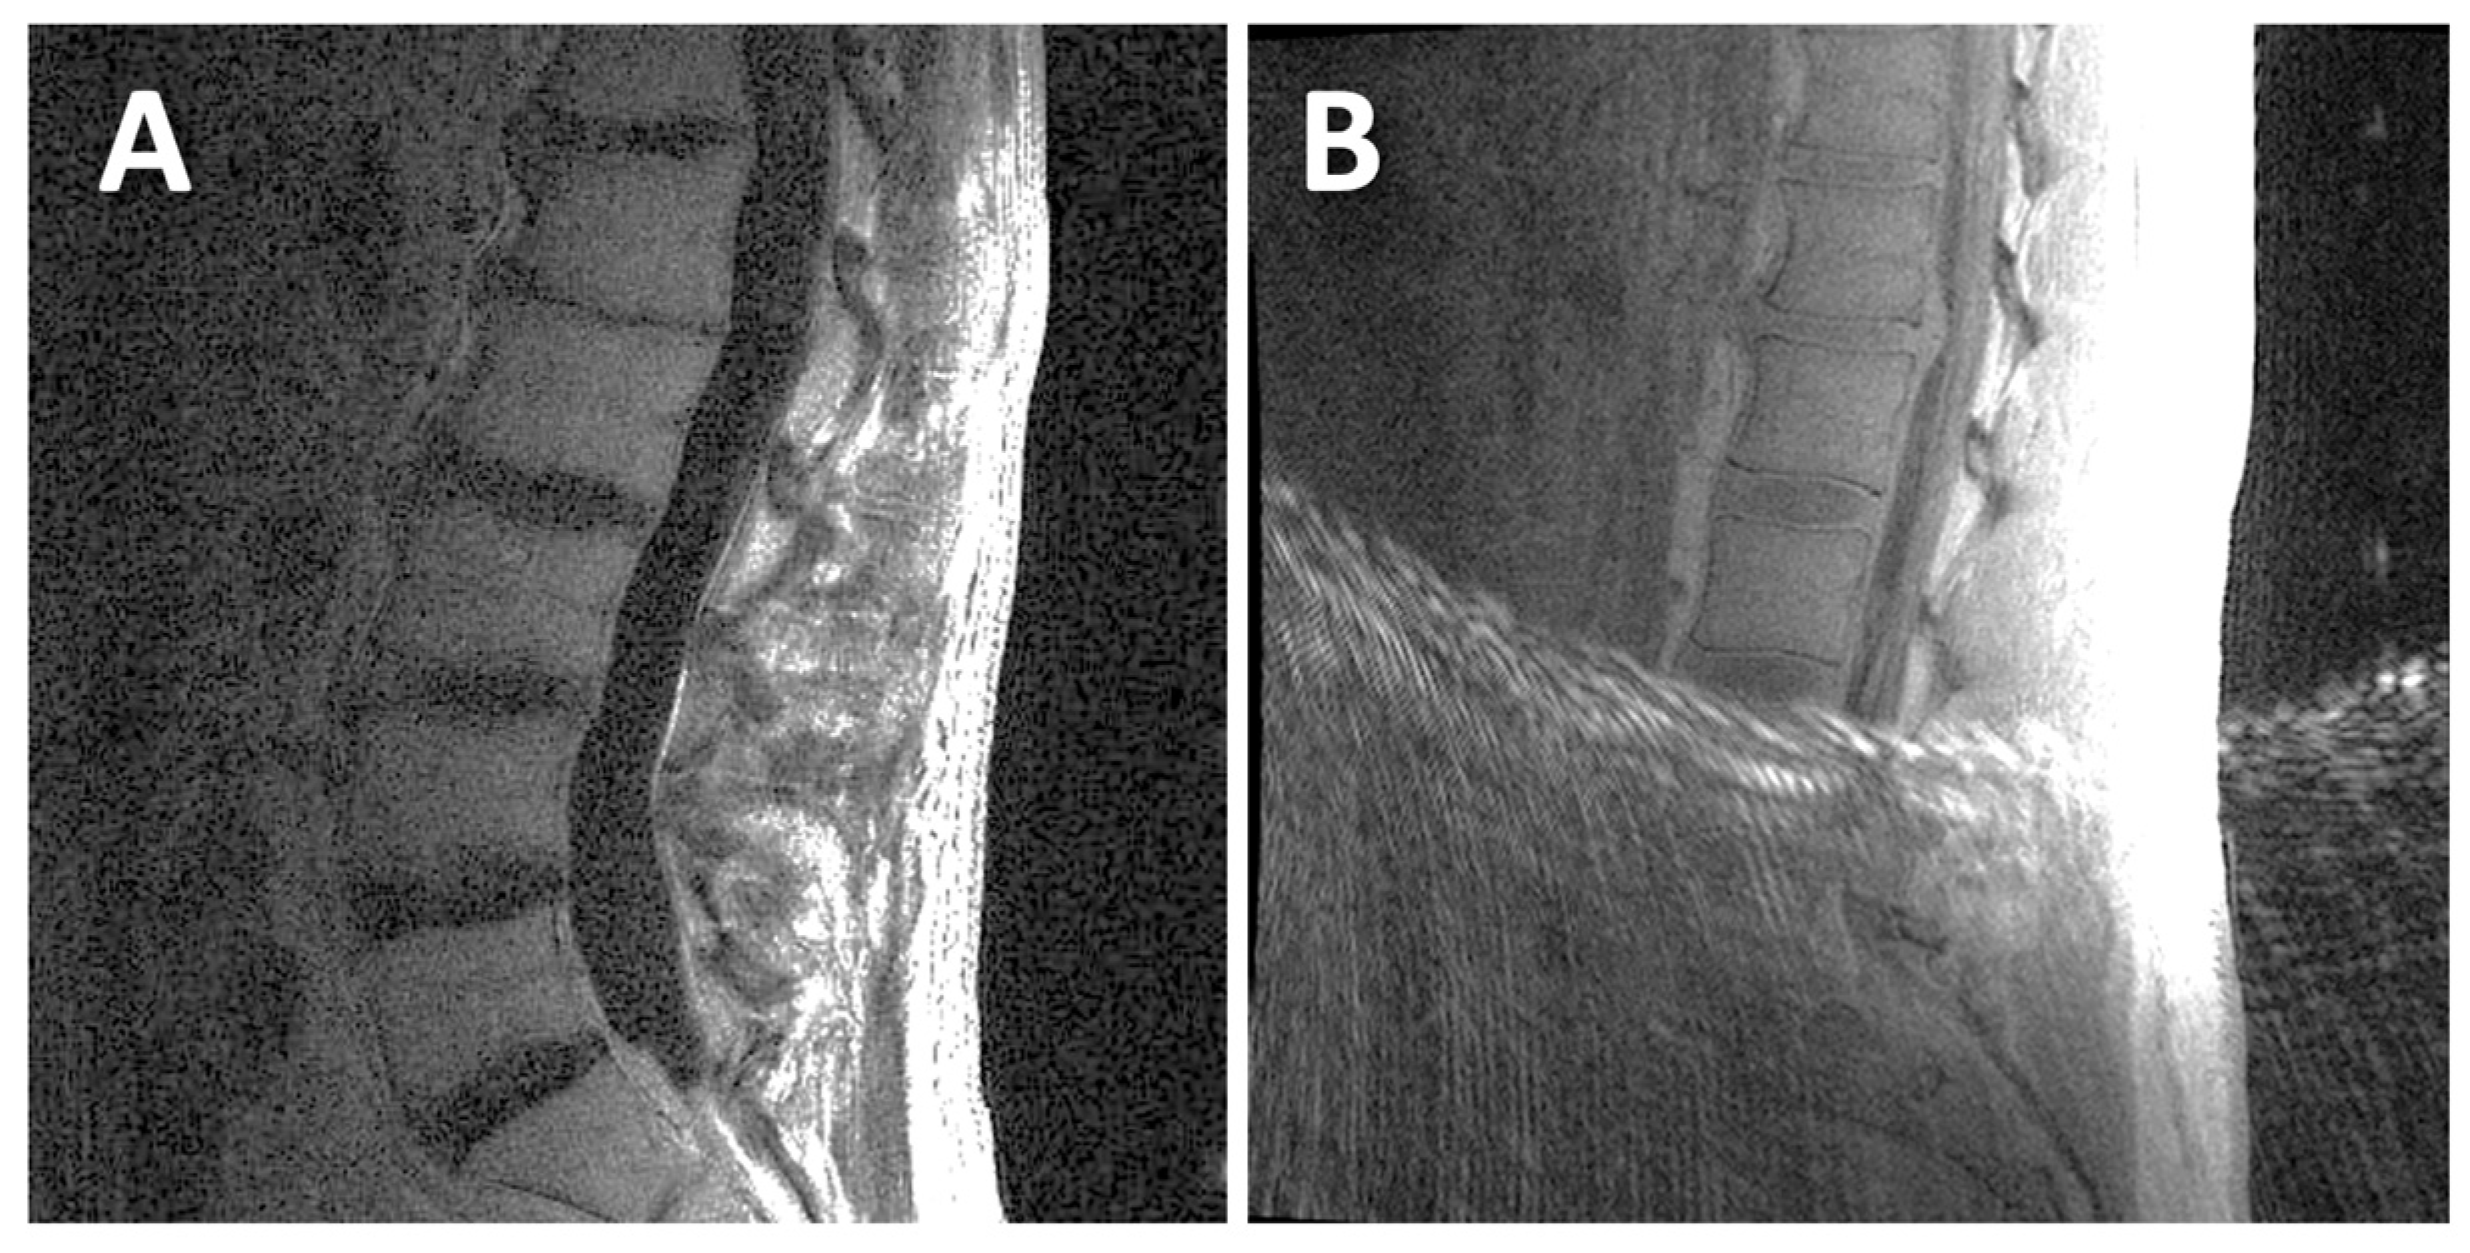

- Finkenstaedt, T.; Siriwananrangsun, P.; Masuda, K.; Bydder, G.M.; Chen, K.C.; Bae, W.C. Ultrashort time-to-echo MR morphology of cartilaginous endplate correlates with disc degeneration in the lumbar spine. Eur. Spine J. 2023, 32, 2358–2367. [Google Scholar] [CrossRef]

- Robson, M.D.; Gatehouse, P.D.; Bydder, M.; Bydder, G.M. Magnetic resonance: An introduction to ultrashort TE (UTE) imaging. J. Comput. Assist. Tomogr. 2003, 27, 825–846. [Google Scholar] [CrossRef]

- Chen, K.C.; Tran, B.; Biswas, R.; Statum, S.; Masuda, K.; Chung, C.B.; Bae, W.C. Evaluation of the disco-vertebral junction using ultrashort time-to-echo magnetic resonance imaging: Inter-reader agreement and association with vertebral endplate lesions. Skelet. Radiol. 2016, 45, 1249–1256. [Google Scholar] [CrossRef] [PubMed]

- Law, T.; Anthony, M.P.; Chan, Q.; Samartzis, D.; Kim, M.; Cheung, K.M.; Khong, P.L. Ultrashort time-to-echo MRI of the cartilaginous endplate: Technique and association with intervertebral disc degeneration. J. Med. Imaging Radiat. Oncol. 2013, 57, 427–434. [Google Scholar] [CrossRef] [PubMed]

- Ji, Z.; Li, Y.; Dou, W.; Zhu, Y.; Shi, Y.; Zou, Y. Ultra-short echo time MR imaging in assessing cartilage endplate damage and relationship between its lesion and disc degeneration for chronic low back pain patients. BMC Med. Imaging 2023, 23, 60. [Google Scholar] [CrossRef]